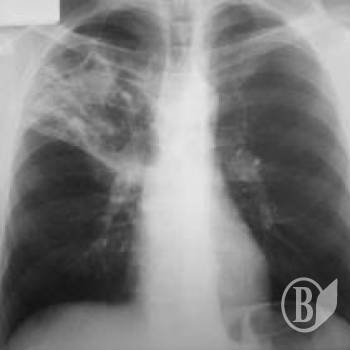

Найбільш розповсюдженими у 2012 році були хвороби органів дихання.

Захворюваність на них становила 33,3 тис. випадків на 100 тис. населення.

А також травми, отруєння та деякі інші наслідки дії зовнішніх причин – 5,4 тис.; хвороби системи кровообігу – 4,5 тис.; шкіри та підшкірної клітковини – 4,1 тис.; сечостатевої системи, ока та його придаткового апарату – 3,6 тис. випадків по кожному класу захворювань; кістково-м’язової системи та сполучної тканини – 3,4 тис.